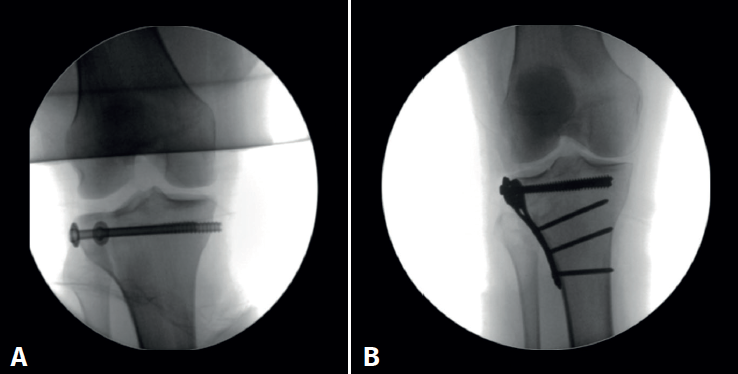

Standard anterolateral and anteromedial portals are created adjacent to the patellar tendon and the joint is visualized with a 30° arthroscope while the knee is insufflated with normal saline. A diagnostic arthroscopy is performed to confirm the TPF, the step-off and the presence of associated lesions (Figure 2). An arthroscopic shaver is inserted into the knee to clear the debris and improve visualization. Next, a small longitudinal anterolateral skin approach is performed, and the fractures are fixed with cancellous screws and/or a buttress plate applied on the external side (minimally invasive plate osteosynthesis), according to the type of fracture diagnosed (Figure 3). Arthroscopy is used to assist reduction and, when needed, to treat soft tissue injuries. The senior authors prefer to perform meniscal repair or partial meniscectomy before bone fixation due to the better visualization of the meniscus. Conversely, ligamentous reconstructions are performed after arthroscopically assisted fixation to ensure bony stability.

Figure 3. Schatzker I tibial plateau fracture fixed with cancellous screws (A) and Schatzker II tibial plateau fracture treated with a buttress plate (B) applied to the external side.